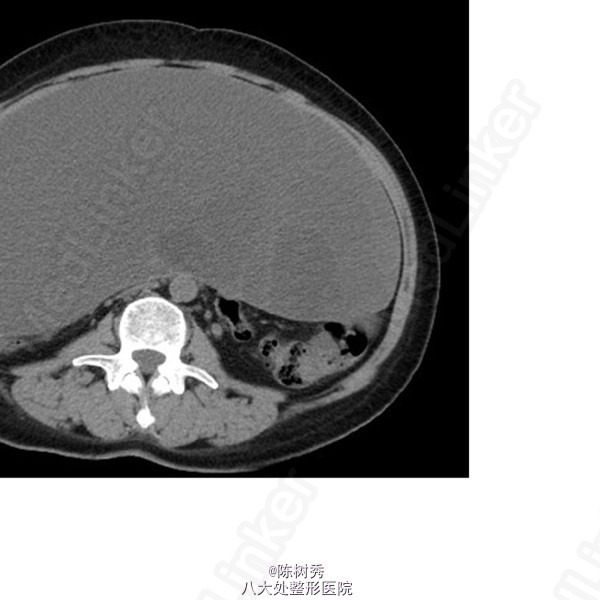

入院后,化验:血常规:白细胞:15600/mm3,嗜酸性粒细胞分数:20.3%; ESR 69 mm, CRP 176 mg/l,风湿因子:656 UI/ml,pANCA antibodies 阳性. 行肺CT:见双肺多发呈类圆形内部稍低密度影,大小不一,较大者约3.2*2.6cm(图1)。考虑肺泡出血和嗜酸性粒细胞侵润。鼻黏膜活检病理证明大量嗜酸性粒细胞侵润。根据上述,诊断为嗜酸性肉芽肿性多血管炎(EGPA,eosinphilic granulomatosis with polyangiitis)。予激素和免疫抑制剂等对症治疗。患者激素减量过程中出现咳血反复,周身及肛周出现溃疡破溃,再次与甲强龙500mg冲击后症状缓解,口腔及肛周、下肢溃烂均较前好转。进食软食一天后突然出现腹痛、发热,腹膜炎症状,查体:全腹压痛,以下腹部为重,伴有反跳痛及肌紧张。完善全腹CT检查考虑消化道穿孔(图2),EGPA并发穿孔的患者行剖腹探查,小肠穿孔修补术。术中见:腹腔小肠肠管明显扩张,多处脓苔,广泛粘连,腹腔内黄绿色渗出100ml,吸尽渗出探查,见距回盲部5cm至距TREITZ韧带150cm之间小肠多发穿孔共11处,较大者破孔3cm*3cm(图3),较小者0.4*0.4cm,予以4-0可吸收线沿肠壁横轴缝合肠壁全层及浆肌层。病理(图4):(小肠穿孔周缘)炎性肉芽组织。术后予以禁食水抗炎补液抑酸及激素治疗。术后6天因血管炎病情反复发作,出现发热,皮肤红斑,7天出现肠瘘,予以双腔套管持续冲洗接负压吸引后逐步愈合后出院。继续风湿免疫科随诊治疗。未有再次发生消化道穿孔。

从图片上看一处破口大小3cm×3cm,肠管边缘紫红色。本人认为应该行局部肠管切口吻合术为好。